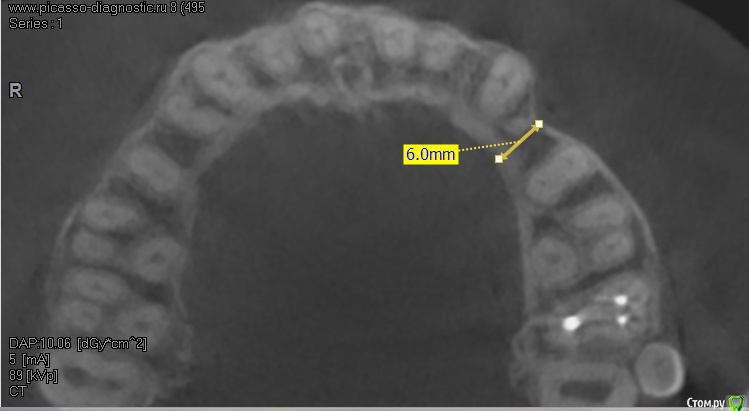

roberttm Опубликовано 26 ноября, 2015 Поделиться Опубликовано 26 ноября, 2015 Доброго времени суток, уважаемые знатоки и профессионалы. Наконец-таки, спустя более чем пять лет после удаления зуба, решился и кое-как начал предпринимать первые шаги на пути к имплантации Отсутствует зуб на верхней челюсти, за клыком. Сделал КТ. Костной ткани немного, как по высоте, так и по толщине. Был в двух клиниках, врачи дают разные рекомендации и, соответственно, планы лечения - я несколько растерялся, Первый вариант: сделать костную пластику (подсадку), установить имплант Dentium высотой 5 мм. Второй вариант: сделать костную пластику (подсадку), открытый синуслифтинг, установить имплант MIS высотой 8 мм. С одной стороны, я, как дилетант, согласен с позицией, что имплант высотой 8мм будет более устойчивым по сравнению с 5мм. Но в первой клинике врач заверил, что якобы есть клинические испытания и доказано, что имплант выстой 5мм ничуть не хуже по устойчивости по сравнению с имплантом высотой 8 мм и выше. Так ли это? Плюс ко всему за счет того, что нет необходимости в открытом синуслифтинге, суммарные затраты первого варианты выходят ниже второго.В общем я в растерянности и прошу высказать свое мнение. Ссылка на комментарий

roberttm Опубликовано 27 ноября, 2015 Автор Поделиться Опубликовано 27 ноября, 2015 Вот ссылка на образ самого диска https://yadi.sk/d/-Pn1ixg1ko3ztВот ссылка на архив с файлами - предположительно основными данными https://yadi.sk/d/8n7lO0GNko46R Касательно самого вопроса относительно высоты имплатна. Не исключаю, что в моем случае имплант высотой 5мм, может, и слишком мал, но тем не менее - все-таки большая ли разница в прочности установки имплантов высотой 5 и 8 мм? Если, например, проводить аналогию с гвоздем - то чем он длиннее, тем больше нагрузку он может выдержать, но тем не менее есть предел, который будет определяться не столько его высотой, сколько прочностью самого материала (стали). Можно ли провести такую параллель для импланта, или, например, 5мм - этот тот допустимый критичный минимум, при котором сохраняется соизмеримая прочность установленного импланта? Ссылка на комментарий